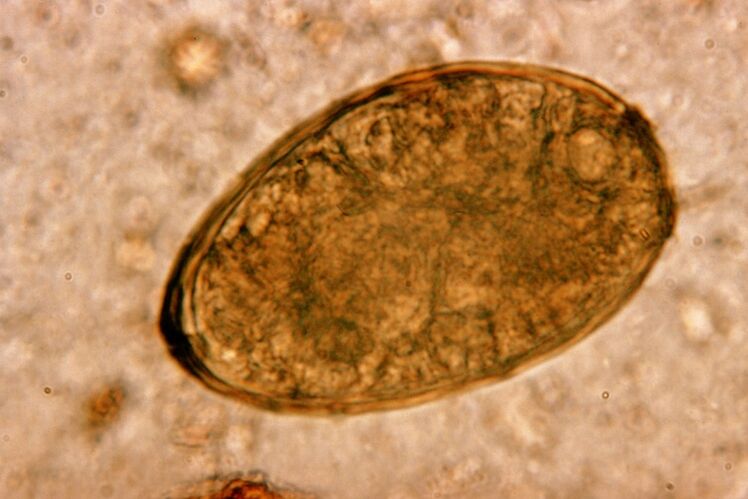

De Fluke lieft an de Lunge a Paart, a bilden Zysten an de Bronchien. Infestatioun geschitt beim Iessen vu Krabben a Kriibsen, déi mam Parasit infizéiert sinn. Eemol am Magen-Darmtrakt penetréiert de Pulmonalfluke de Peritoneum an erreecht d'Lunge duerch d'Membran, wat e persistent Hust am Patient verursaacht.

Déi kleng Helminth pulmonal Floss, déi zu der Klass vun Trematoden gehéiert, "spezialiséiert" op Parasitiséierung speziell an de Lunge. Et verursaacht vill méi sérieux Problemer am Atmungssystem wéi Ronnwürmer, zum Beispill.

Op der Plaz vu senger Lokalisatioun erschéngen Infiltrate an Blutungen entwéckelen, als Resultat vun deenen Huelraim erschéngen mat zerfallende Metaboliten vu Würmer, doudege Parasiten a Lungegewebe gefëllt. De Schued vum Pulmonalfluke gëtt weider verschäerft duerch d'Tatsaach datt et eng laang Liewer ass a kann am Kierper vum Host bis zu 20 Joer liewen.

Fir mat dësem geféierleche Parasit ëmzegoen, ass d'Behandlung ënner strenger Opsiicht vun engem Dokter noutwendeg. Nëmmen hien kann eng efficace Medezin wielen, déi fir all Fall anescht ginn soll.